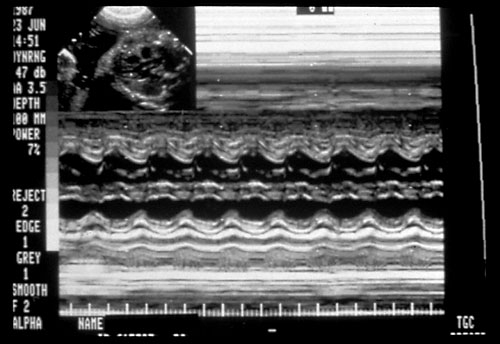

Absent umbilical artery blood

flow in severe growth delay

Reversed umbilical artery blood

2. Umbilical Arteries — contains 40% of fetal ventricular output in both arteries. Traditionally the systolic flow to diastolic flow or S/D ratio has been used to monitor fetuses at risk. The umbilical Doppler has been particularly useful in managing patients with IUGR, preeclampsia, complicated medical illnesses (diabetes, lupus, etc). (Harrington K, Carpenter RG, Nguyen M, Campbell S. Changes observed in Doppler studies of the fetal circulation in pregnancies complicated by pre-eclampsia or the delivery of a small-for-gestational baby. I. Cross-sectional analysis. Ultrasound Obstet Gynecol 1995;6:19-28. & Pattinson RC, Norman K, Odendaal HJ. The role of Doppler velocimetry in the management of high risk pregnancies. Br J Obstet Gynaecol 1994;101:114-120. & Trudinger BJ, Cook CM, Giles WB, Ng S, Fong E, Connelly A, Wilcox W. Fetal umbilical artery velocity waveforms and subsequent neonatal outcome. Br J Obstet Gynaecol 1991;98:378-84) The ranges are gestationally determined with slightly higher S/D ratios (> 2.5-4.0) in early gestations prior to 24 weeks and the lower S/D ratios ( < 3.0) greater 24 weeks. The absence of end diastolic or reversed end diastolic flow is particularly worrisome. Most believe that the absence or reversed flow in the umbilical artery S/D ratio means a very high risk of stillbirth within 48-72 hours. (Karsdorp VH, Van Vugt JM, van Geijn HP, Kostense PJ, Arduini D, Montenegro N, Todros T. Clinical significance of absent or reversed end diastolic velocity waveforms in umbilical artery. Lancet 1994;344:1664-8 & Kurkinen-Raty M, Kivela A, Jouppila P. The clinical significance of an absent end-diastolic velocity in the umbilical artery detected before the 34th week of pregnancy. Acta Obstet Gynecol Scand 1997;76:398-404)

More recently, the pulsatility index (PI) has been used since it is not affected by the reverse or absence of end-diastolic flow. Reference ranges are used for the 5th and 95th percentiles. (Harrington K, Carpenter RG, Nguyen M, Campbell S. Changes observed in Doppler studies of the fetal circulation in pregnancies complicated by pre-eclampsia or the delivery of a small-for-gestational baby. I. Cross-sectional analysis. Ultrasound Obstet Gynecol 1995;6:19-28.)